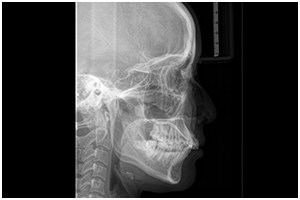

治療設備が充実していることは、当院のメリットの一つです。インプラント治療においては事前の精密検査が大切であり、当院では歯科用CT、セファロ(ケースによる)、口腔内スキャナー(プライムスキャン2)、マイクロスコープなどの先端設備を活用して検査します。精度の高い検査・処置を通じて、患者さんに適した治療計画をご提案いたします。

頭や顎の骨格のバランス、前歯の角度、噛み合わせの状態などを調べるための頭部のレントゲン写真です。